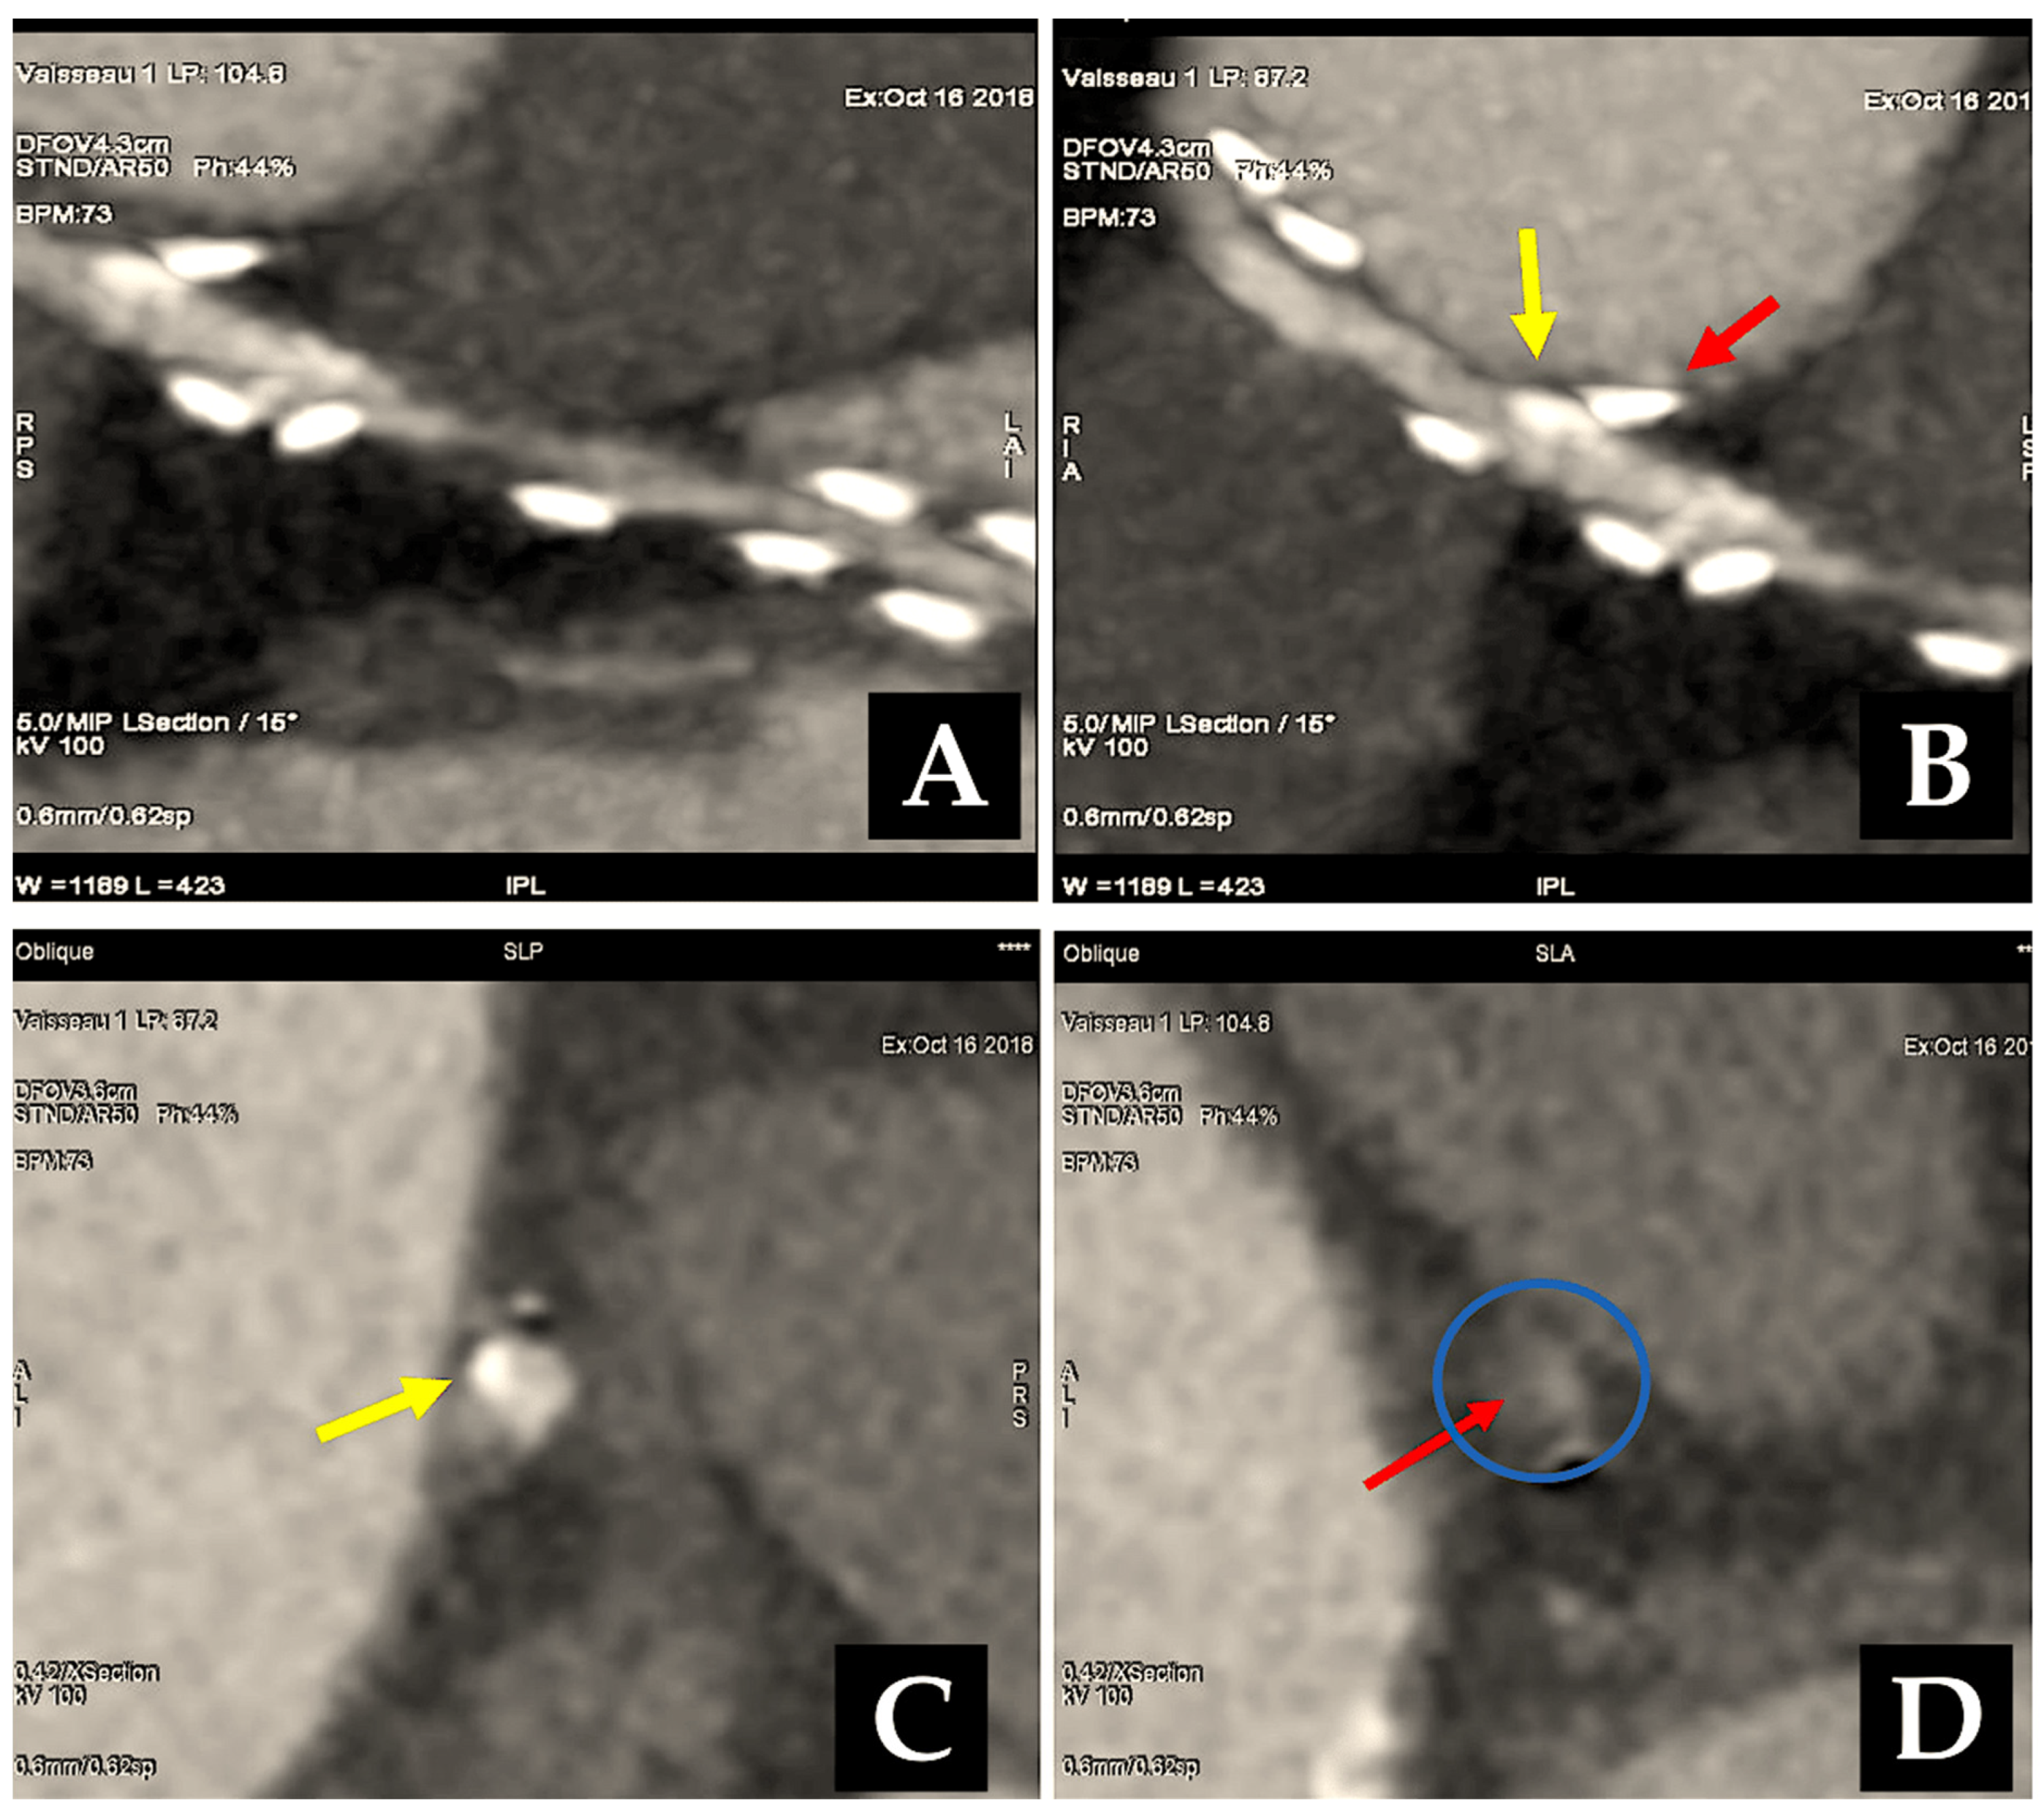

- Mounsey, C.A.; Mawhinney, J.A.; Werner, R.S.; Taggart, D.P. Does previous transradial catheterization preclude use of the radial artery as a conduit in coronary artery bypass surgery? Circulation 2016, 134, 681–688. [Google Scholar] [CrossRef]

- Staniloae, C.S.; Mody, K.P.; Sanghvi, K.; Mindrescu, C.; Coppola, J.T.; Antonescu, C.R.; Shah, S.; Patel, T. Histopathologic changes of the radial artery wall secondary to transradial catheterization. Vasc. Health Risk Manag. 2009, 5, 527–532. [Google Scholar] [CrossRef]